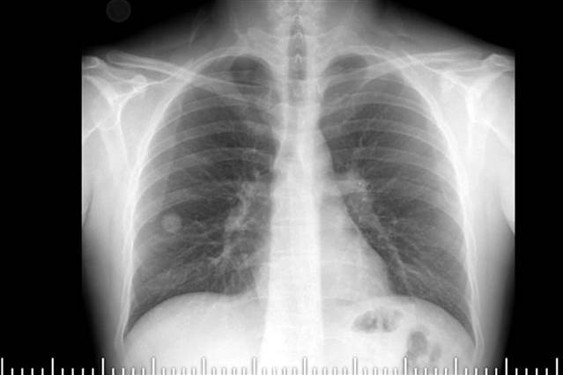

Elazığ Fethi Sekin Şehir Hastanesi Göğüs Cerrahisi Polikliniği'ne göğüs ağrısı ve öksürük şikayetiyle başvuran Topuz'un çekilen tomografisinde, sağ akciğer orta lobunda 2 santimetre büyüklüğünde tümör olduğu tespit edildi.

Hastanın yapılan takibinde akciğerindeki tümörün büyüdüğünün gözlenmesi üzerine, kanserli hücre olabileceği şüphelenilen doku operasyonla alındı.